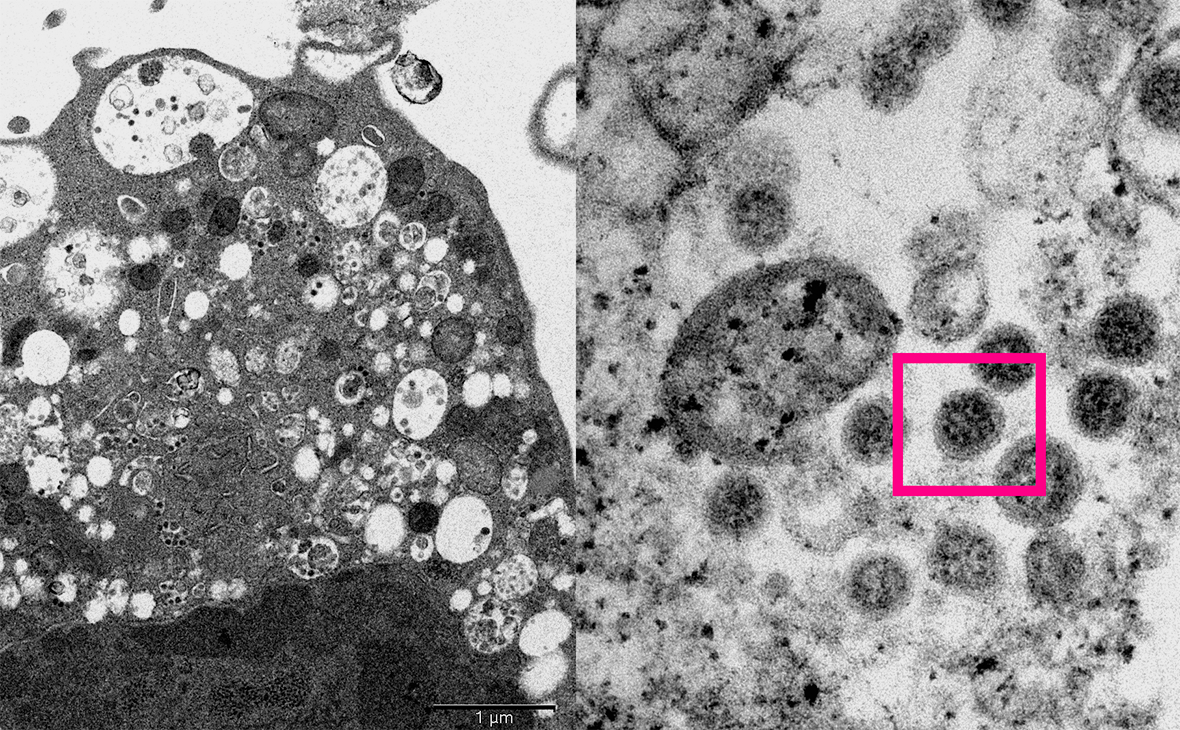

Фото: med.hku.hk